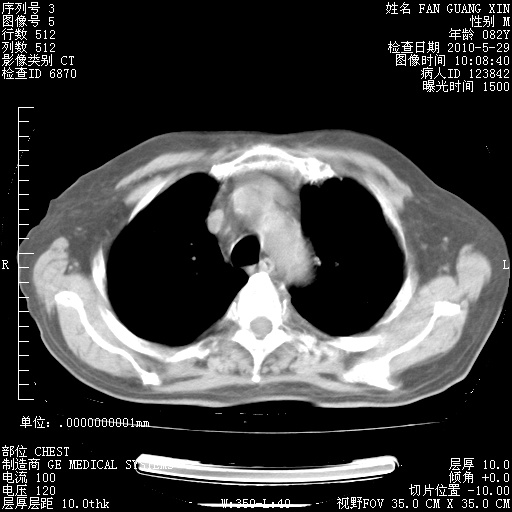

还需要哪些辅助检查?我们医院排除真菌感染没有任何检验方法,胸片好像能够排除肺部真菌感染。